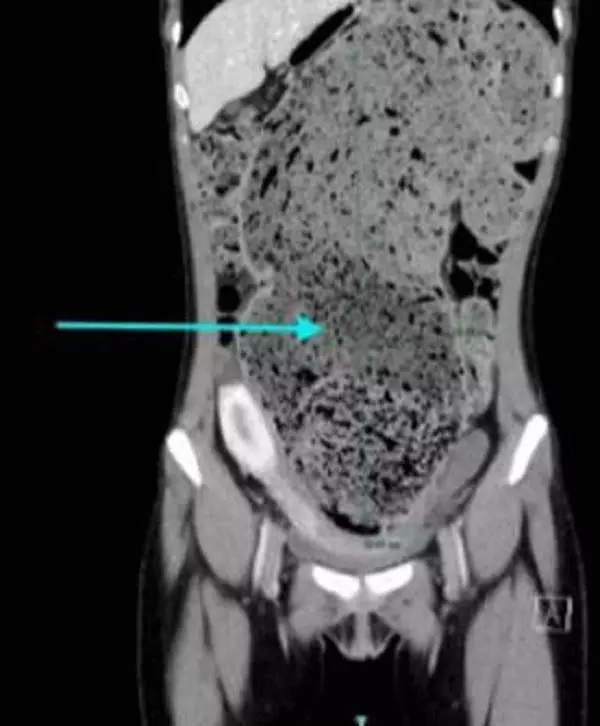

미국 사우스 쇼어 대학병원 내과 의료진에 따르면, 25세 여성이 4개월 동안 지속된 만성 변비로 극심한 복부 팽만감과 통증을 느꼈다. 증상이 낫지 않자 병원을 찾아 각종 검사를 받았다. 충격적이게도 CT 검사 결과, 여성의 대장에 대변이 굳어 찬 ‘대변 매복’ 상태임을 확인했다. 대변 매복은 대변이 장에 굳어서 단단히 막혀 스스로 배변이 어려워지는 심각한 변비 상태를 말한다. 특히 지름 약 15cm의 지나치게 늘어난 S자 결장(대장의 주요 부분)이 발견됐다. 이로 인해 내시경도 들어가지 못할 정도로 대변이 굳어 장이 막힌 상태였다.

의료진은 전신마취 상태에서 손으로 직접 굳은 대변을 꺼내는 수동적 대변 제거 시술을 진행했다. 시술 이후에는 장을 정화하는 데 도움이 되는 약물 치료를 받았다. 또 여성은 입원 기간 동안 약 5kg의 체중을 감량했다. 의료진은 “만성 변비의 흔한 원인으로 섬유소 부족, 탈수, 움직임 부족, 스트레스 등이 있다”며 “변비와 함께 복부 팽만, 통증, 체중 감소 등의 증상이 지속된다면 반드시 진료를 받아야 한다”고 말했다.